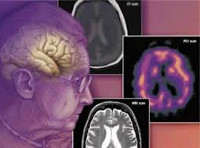

На КТ и МРТ головного мозга при деменции появляются поля лейкоареоза, состояния, представляющего собой локальное снижение плотности мозгового вещества. Лейкоареоз может быть субкортикальным, в виде множественных очагов в глубинных отделах, либо перивентрикулярным, возле полюсов боковых желудочков мозга.

Время, за которое поражение мозга достигает значительного уровня, зависит от возраста пациента. Мозг пожилых людей острее реагирует на происходящие изменения. Значительно снижается уровень церебральной перфузии. Из-за диффузной гибели аксонов и утраты синаптических связей быстрее прогрессирует разобщение подкорковых образований и лобных отделов. Лейкоареоз при ДЭ выглядит как «пятнистые» очаги с низкой интенсивностью, располагающиеся преимущественно возле боковых желудочков и в глубоких отделах. Часто на КТ, МРТ можно увидеть диффузные гипоинтенсивные изменения, отличающиеся симметричностью, в районе семиовального центра. Изредка встречаются лакунарные инфаркты, не прозвучавшие клинически.

Для выявления и оценки тяжести заболеваний, спровоцировавших развитие сосудистой деменции, больных направляют на консультацию к неврологу, кардиологу, психиатру и другим специалистам. Осуществляют мониторинг артериального давления. Пациентам с сосудистой деменцией назначают МРТ головного мозга, КТ головного мозга, УЗДГ сосудов головного мозга, РЭГ, ЭЭГ и другие исследования. Дифференциальную диагностику проводят с деменцией при болезни Альцгеймера. В пользу сосудистой деменции свидетельствует наличие неврологических нарушений и нерезко выраженные нарушения памяти. При постановке диагноза учитывают возможность развития смешанной деменции, обусловленной как сосудистой патологией, так и болезнью Альцгеймера.